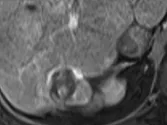

Figure 8. Carcinome hépatocellulaire. Sur l’examen initial (A, B), on observe

une lésion faiblement rehaussée au temps artériel (A), mais avec un lavage

évident au temps portal (B). Après six mois de chimiothérapie (C, D), la lésion est moins hypervascularisée au temps artériel (C), et de larges plages de nécrose sont apparues aux temps artériel et portal (D). La lésion est « PR » selon mRECIST